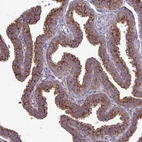

Immunohistochemistry analysis in human fallopian tube and pancreas tissues using HPA050918 antibody. Corresponding CLTA RNA-seq data are presented for the same tissues.